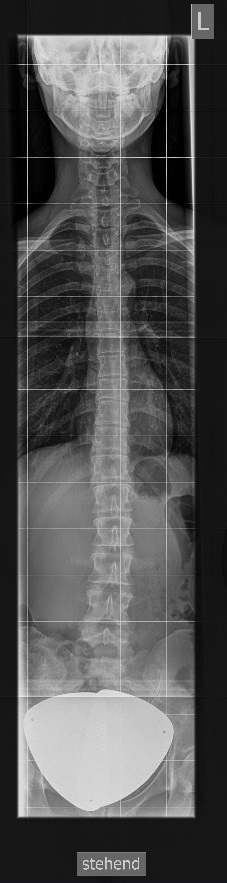

Wirbelsäule Ganzaufnahme a.p.

Es wurden keine Bilder gefunden.

Kassette/Abstand

Format 3 x 35/43 im Ganzbein- WSstativ oder 30/120 Rasterkassette / FFA 3m

Lagerung

Patient steht aufrecht mit dem Rücken am Rasterwandstativ, Kopf leicht nach hinten nehmen.

Zentralstrahl

Senkrecht auf Wirbelsäule. Aufblendung von Oberlippe bis einschließlich Hüftköpfe.

Qualitätskriterien

HWS-BWS-LWS mit Sakrum sollte vollständig und gut beurteilbar abgebildet sein.

Indikation

Beurteilung der Wirbelsäule und des Beckens bei Schiefstand.

Anmerkung

Spezialstativ mit Raster oder Digitalaufnahme mit Abbildung eines Rasters zur Vermessung. Evtl Ausgleichschuhe ausziehen und auch ggf. Verlaufsfilter für guten Kontrast verwenden.